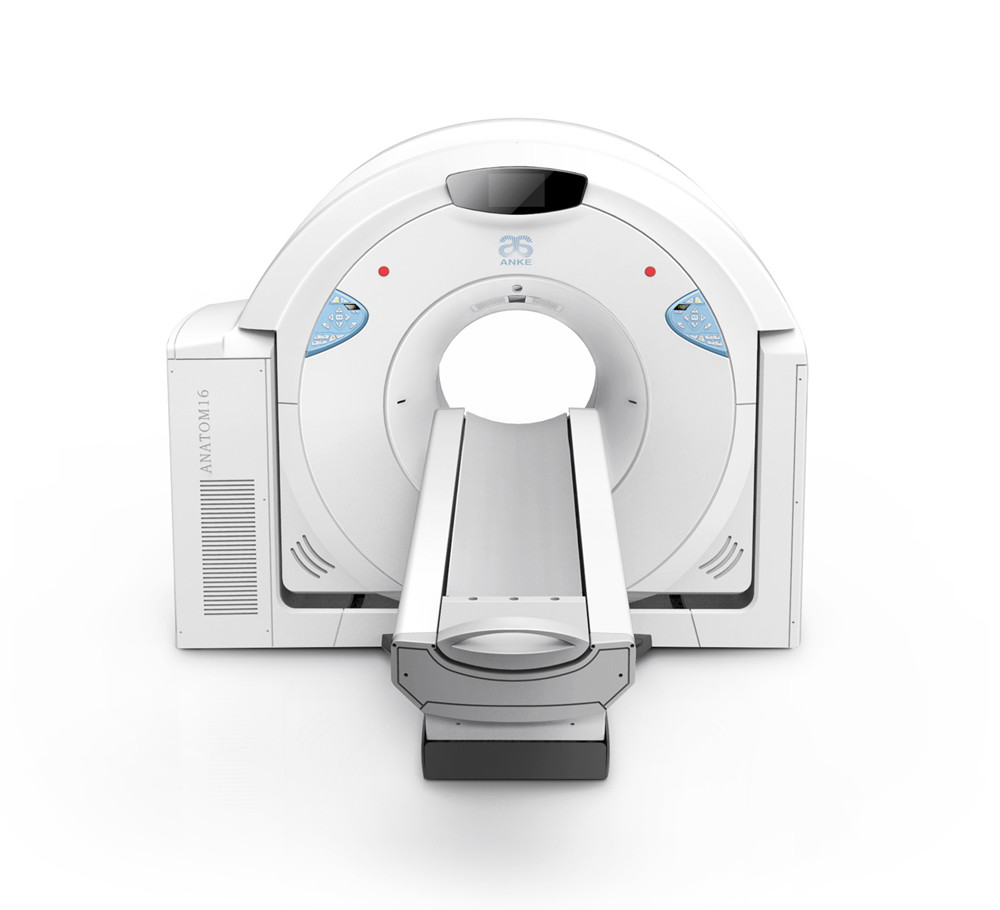

案例展示 ∥ 影像类设备 ∥ ANATOM 16层螺旋CT

作为国内资深的CT生产厂家,该机型具备了与国际主流产品相同的技术能力,为此需要开发全新的产品外观及结构,以适应新的产品形象。大型医疗器械涉及到材料,力学,工艺,运动机构,人机功效等不同的各种学科知识,无限空间设计团队为了整合不同学科要求而做出平衡性设计,同时突出设计亮点,为产品赋予自身特有的产品形象。

ANATOM 16层螺旋CT是针对国内基层医疗机构对高端CT的需求而推出一款划时代产品,采用了十多项创新性技术,它对于我们国内广大县乡日益增加的肿瘤、心脑血管疾病等诊断有着重要意义,凭借卓越的影像质量,ANATOM 16可以帮助医生进行早期、微小病变以及心脑血管疾病等全身各个系统的诊断及筛查,进而给患者及时恰当的治疗,为患者的早期治疗赢得时机。

客户 | 安科医疗

项目 | ANATOM 16层螺旋CT

年份 | 2013

client | ANKE Tech

year | 2013